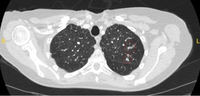

Computed tomography (CT) showing two areas (red circles) of mucoid impaction of the left upper lobe subsegmental bronchi, resulting in appearance that mimics a nodule

From the collection of Dr George Tsaknis, MD, PhD, FRCP(London), MRQA, MAcadMEd, PGCert; used with permission